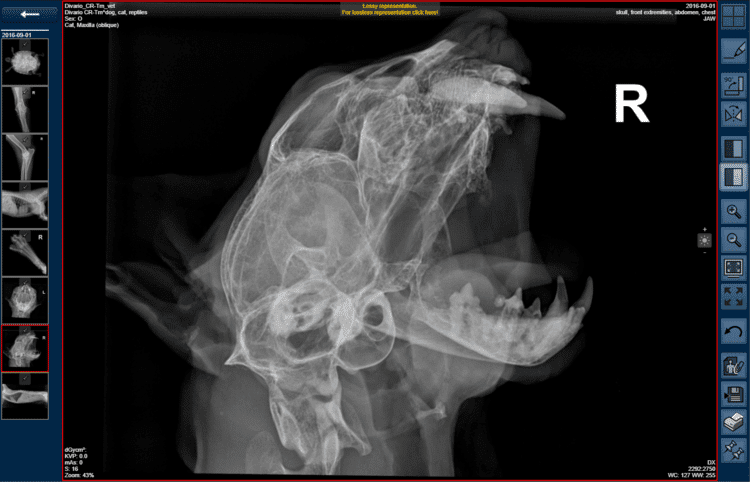

At Nuon Imaging, we know that veterinary radiology brings unique demands—whether you’re caring for a Chihuahua, a Clydesdale, or an exotic patient. That’s why we provide imaging systems, software, and support designed specifically for veterinary workflows.

Explore our wide selection of Veterinary Radiology Equipment—from stationary DR systems built for high-volume clinics to portable X-ray units for mobile and equine care. Every system we provide is selected for image quality, durability, and workflow efficiency—so you can deliver faster diagnoses and better care for your patients.

NuonVet™ software is built from the ground up for veterinary imaging. Whether you’re working in a busy small animal clinic, capturing large animal images in the field, or managing a mixed practice, NuonVet™ helps you deliver faster diagnoses and better patient outcomes.

With species-specific annotation tools, workflow-friendly integration with your PACS and practice management system, and options for both local and cloud-based access, it’s the imaging software trusted by veterinary teams across Canada.